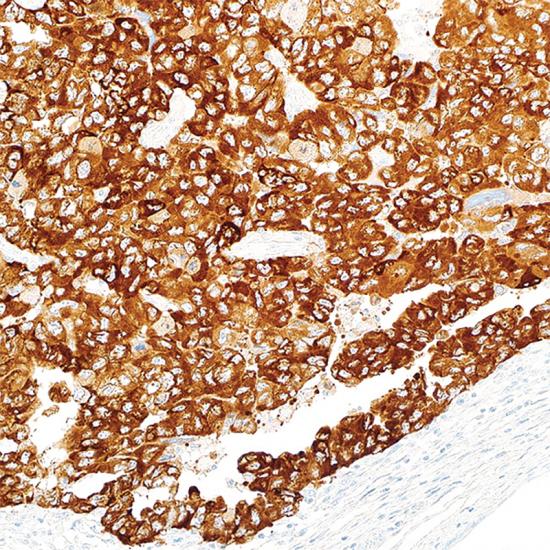

LIN28

LIN28抗體試劑(免疫組織化學法) 閩廈械備20200023號

• 陽性部位:

細胞漿

• 陽性對照:

卵黃囊腫瘤

Lin28是一種高度保守的RNA結合蛋白,可以與miRNA家族中l(wèi)et-7家族的前體RNA的終末環(huán)相結合,并阻斷l(xiāng)et-7的成熟過程。Lin28高表達的腫瘤多呈現(xiàn)低分化,預后較差。LIN28常與SALL4聯(lián)合用于生殖細胞腫瘤和非生殖細胞起源腫瘤的鑒別。